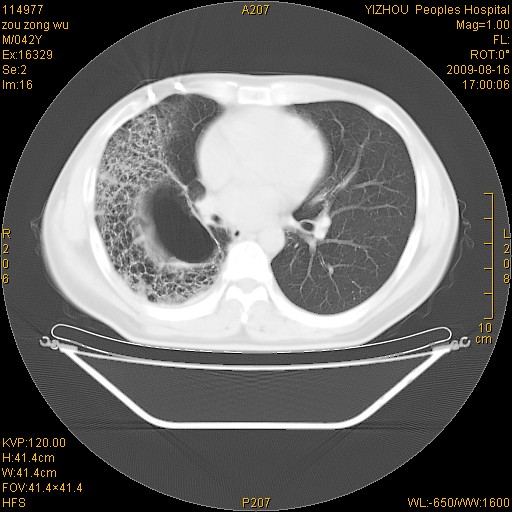

以下是引用zjzjr在2009-8-17 10:42:00的发言:[br]右侧间质性肺炎伴纤维化,右肺下叶肺囊肿伴感染(不除外外伤后引起),右肺野及胸壁软组织\\肝内见多发斑点状,中枪了吧.右侧胸膜肥厚\\粘连.